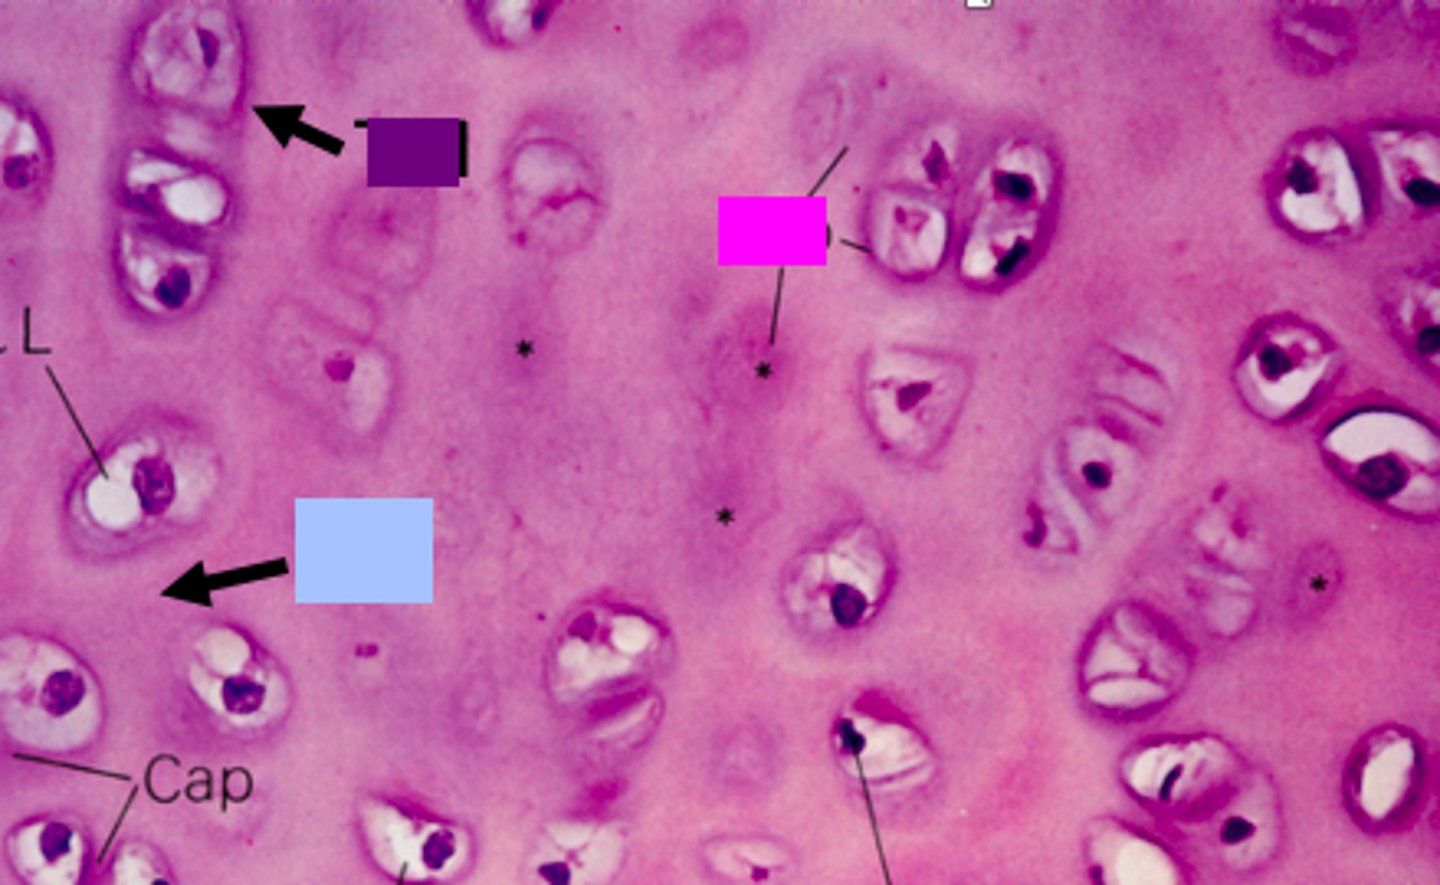

isogenous groups

identify the pink box:

<p>identify the pink box:</p>

interterritorial matrix

identify the blue box:

<p>identify the blue box:</p>

territorial matrix

identify the purple box:

<p>identify the purple box:</p>